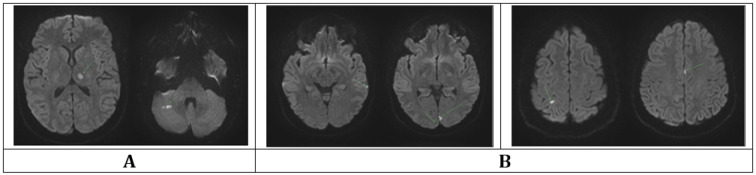

臭氧疗法通常作为一种增强免疫力的替代疗法在市场上销售,缺乏强有力的疗效证据,并存在重大的安全风险。尽管声称它有治疗效果,但监管机构,如美国食品和药物管理局(FDA),警告不要使用它,因为它具有毒性,而且在可容忍的暴露水平下缺乏证明的益处。本病例报告强调了严重的神经系统并发症,包括缺血性梗死和持续的认知缺陷,在静脉注射臭氧(O3)治疗后,先前健康的患者。一名36岁的女性在接受静脉臭氧治疗后不久因胸痛、晕厥和全身癫痫发作而就诊于急诊科。诊断成像显示丘脑和小脑多发缺血性梗死,与栓塞事件一致。患者需要重症监护病房(ICU)入院,尽管神经功能有所改善,但经历了持续的认知障碍,需要长期康复。

Ozone therapy, often marketed as an immune-boosting alternative treatment, lacks robust evidence of efficacy and poses significant safety risks. Despite claims of therapeutic benefits, Regulatory agencies, such as the U.S. Food and Drug Administration (FDA), warn against its use due to its toxic properties and lack of proven benefits at tolerable exposure levels. This case report highlights severe neurological complications, including ischemic infarcts and persistent cognitive deficits, following intravenous ozone (O3) therapy in a previously healthy patient. A 36-year-old woman presented to the emergency department with chest pain, syncope, and generalized seizure shortly after receiving intravenous ozone therapy. Diagnostic imaging revealed multiple ischemic infarcts in the thalamus and cerebellum, consistent with an embolic event. The patient required intensive care unit (ICU) admission, and despite improved neurological function experienced lasting cognitive impairments necessitating long-term rehabilitation.